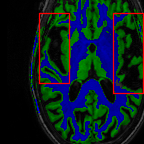

Sparsity LI 2D CNN 3D CNN Ours GT

4 Refer to caption (a) 0.6787/0.7972 Refer to caption (b) 0.8143/0.8776 Refer to caption (c) 0.8190/0.8714 Refer to caption (d) 0.8664/0.9085 Refer to caption (e) GM/WM

Refer to caption (f) 0.6808/0.7161 Refer to caption (g) 0.8103/0.8631 Refer to caption (h) 0.7950/0.8606 Refer to caption (i) 0.8598/0.9115 Refer to caption (j) GM/WM

Figure 6: Visual comparison of gray matter (Green)/white matter (Blue) segmentation over different methods, with respective DICE scores listed under the images.

In Fig. 6, we demonstrate the advantage of the proposed method in brain matter segmentation. It is clear that although 2D and 3D CNN generates visually plausible interpolation as presented in Fig. 5, the brain matters are easily misclassified due to incorrect anatomical structures and blurred details.